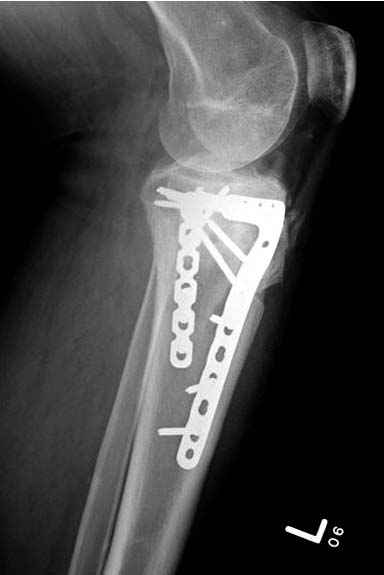

Решили выполнить остеосинтез штифтом и внутрисуставного перелома пластиной и винтами. Жду мнения! Зачем мне оправдываться-я же не преступник. Диалогом называется...

Отдельные переломы тибиал плато и перелом проксимальной трети большеберцовой кости отличаются от переломов тибиал плато с вовлечением диафиза. Здесь перелом тибиал плато типа Schatzker VI, полученный в результате высокоэнергетической травмы. Перелом метафиза образовал отрыв суставной поверхности от диафиза с вовлечением медиального и латерального мыщелков. Двухмыщелковые переломы из-за укрочения опасны развитием компартаментального синдрома, повреждением латерального мениска и связок.

При переломах одного из мыщелков тибиал плато+дополнительный перелом проксимальной трети большеберцовой кости можно применить комбинированный вариант фиксации, т.е. мыщелок винтами или пластиной, а для диафиза можно установить гвоздь. В данном варианте потеряно преимущество гвоздя , из-за серьезной травмы суставной поверхности нельзя нагружать ногу несколько месяцев. А без нагрузки гвоздь просто заполнитель пространства внутри кости!

На вашем место я бы подождал с фиксацией до готовности кожных покровов, и за это время можно было подобрать соответствующий фиксатор, т.е более длинная пластина снаружи и медиальная пластина на апексе перелома как подпорка. Здесь приемлем как раз минимальный доступ.

Имеющаяся импрессия не потребовала пластики - достаточным оказалось поднять отломок

Если там действительная импрессия, пустое место без структуральных заполнителей, кость или синтетические материалы, не восстановится, а образуется коллапс, и ось конечности поведет после нагрузки. Кроме того там возможно "болт стяжка"?, в медиальной стороне выступает за кортекс, можно было укоротить! Потом создается впечатление, что не соответствуют мыщелки большеберцовой и бедренной костей? Покажите снимок.

Здесь пару случаев для сравнения,...в первых 1-4 слайдах метод фиксации одним фиксатором, как видно после 8 месяцев сохранилась ось. С 5 по 9 вариант двумя пластинами...